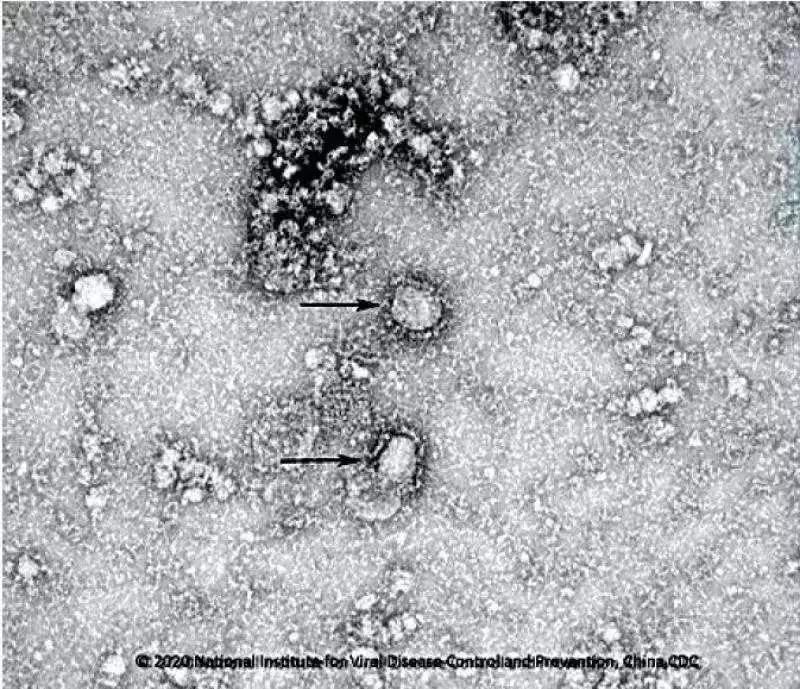

中國(guó)疾控中心開(kāi)始研發(fā)新冠病毒疫苗,已成功分離病毒,正篩選種子毒株。

中國(guó)疾控中心已成功分離我國(guó)首株新型冠狀病毒毒種